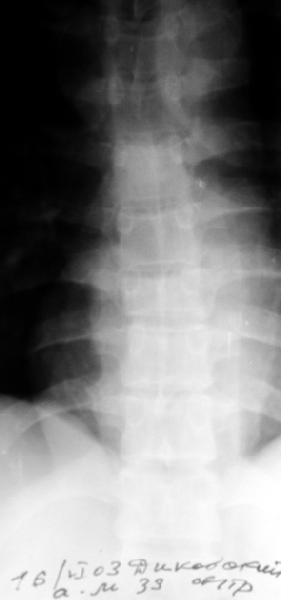

Перелом IX грудного позвонка

Мужчина 39 лет, перевернулся в машине 12 июня. Клинически неврологии нет. Нужна ли репозиция и оперативная фиксация этого повреждения? Если нет, то как вести? Спасибо заранее.Алексей Рунков, УНИИТО

Компрессионный стабильный перелом 2-3 степени, в оперативном лечении не нуждается. Лечение 20-30 дней на вытяжении за подмышки, затем массаж, ЛФк в постели ещё 2 недели, хорошо бы барокамера если есть, затем реклинирующий корсет на год. Ну и ограничения по физической нагрузке.

Looks more than 50% collapse, needs CTscan for better evaluation.

if you don't fuse them they may develop painful kyphosis in the future.

A CT would be helpful to determine if there is middle column involvement. Also it would help determine if the posterior interspinous ligament is intact (lack of interspinous widening. The available images appear to show an anterior column only injury. If other imaging tests confirm this combined with normal neurological function nonoperative treatment with a hyperextension brace or nothing is appropriate.

Agreed, except that loss of posterior vertebral body height on the lateral radiograph suggests middle column involvement as well, and therefore a diagnosis of burst fracture. This is confirmed on the AP by (albeit subtle) widening of the pedicles at the level of injury. In keeping with this diagnosis, the lateral also suggests retropulsion of fracture fragments into the canal. I concur that unless there is associated facet subluxation or interspinous widening on CT (possible, but unlikely given the well-maintained alignment and given that on the AP radiograph the spinous processes seem reasonably equidistant) this is a stable burst fracture that I would treat with a TLSO for 3 months.

This presumablly is a stable compression of the body of T8 or thereabout, without neurology. Keep him in bed until the acute pain subsides and then start him on physiotherapy.

The lack of any neurological sysmptoms suggests that this man has a stable fracture despite losing 50% of his vertebral height. Initial management would be analgesia and bedrest until comfortable, and then the application of a hyperextension brace to prevent kyphosis. With this fitted he can be mobilised and can sit, and provided home situation is reasonable, should be able to go home after only a few days, with the proviso that he is still flat for part of the day. I would expect him to wear the brace for at least 2 months.